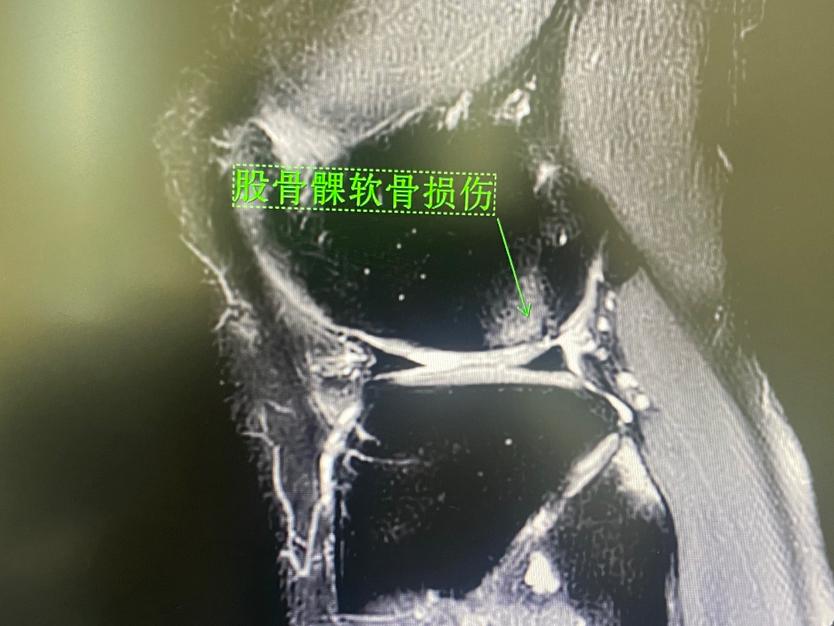

滑车软骨损伤 (软骨剥脱,软骨下骨暴露)

下面展示典型的膝关节软骨损伤,MRI核磁扫描可以清晰发现软骨损伤(3-4度),门诊检查非常常见!